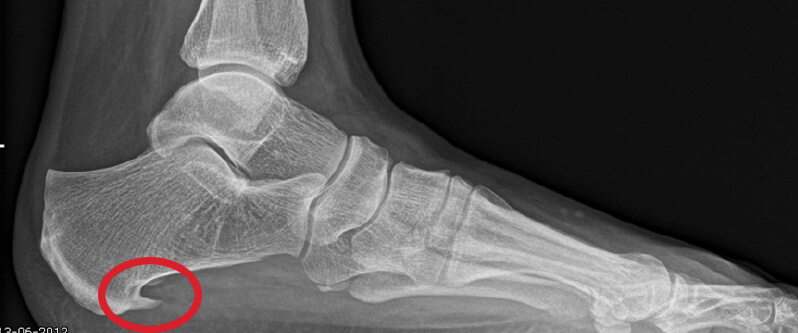

Hielspoor op röntgenfoto

Hielspoor duidelijk zichtbaar op deze op röntgenfoto.

Een hielspoor is een botuitwas (verkalking) aan de onderzijde van het hielbot, het zogenoemde calcaneus. Deze verkalking bevindt zich op de plaats waar de peesplaat onder de voet, de fascia plantaris, aanhecht. Een hielspoor is goed zichtbaar op röntgenfoto’s en kan ook met echografisch onderzoek worden vastgesteld.

Een röntgenfoto kan een hielspoor zichtbaar maken, maar is niet altijd noodzakelijk. Met echografie kan de dikte en kwaliteit van de fascia plantaris worden beoordeeld en kan worden vastgesteld of er sprake is van overbelasting of degeneratie.